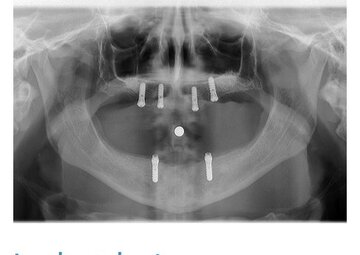

Notre cabinet comprend également un local dédié à la radiologie numérique, incluant une radiographie panoramique, permettant des diagnostics précis et rapides. Grâce à notre équipement de pointe, nous assurons une prise en charge optimale de chaque patient.

• Implantologie : Nous pratiquons la pose d'implants dentaires, offrant ainsi une solution durable et fiable pour le remplacement de dents manquantes.